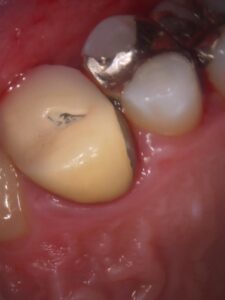

今回は被せ物が欠けた場合の対応についての投稿になります。

歯医者で被せ物(クラウンやインレー)が欠けたときは、放置せず早めに歯科医院で診てもらうことが大切です。欠け方によって対応が変わりますが、一般的な対処法は次の通りです。

③ 被せ物の下に虫歯がある場合

欠けた原因が被せ物の下の虫歯の場合は

虫歯を除去

必要なら土台を作り直す

新しい被せ物を装着

という流れになります。